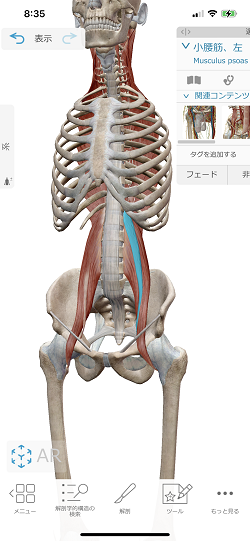

関係する筋肉は『横隔膜』『小腰筋』『大腰筋』です。

小腰筋

小腰筋は約60%の人に存在しない為、大腰筋と合わせて『腸腰筋』と呼んでいますが、これが腰の痛みの原因になっている方が多いのです。